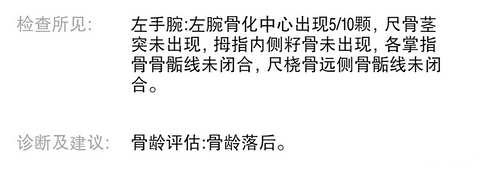

两杯咖啡钱,带娃做个小保健,超值!

俗话说,爹矮矮一个,妈矮矮一窝。每次跟队友探讨娃儿的身高问题,他都嘲笑我拖了,娃儿的后腿 上次我们去儿科骨科看x腿的时候,忘了顺便查一个骨龄,现在每天晚上都要绑腿矫正,说老实话,我始终觉得那个会影响娃儿的身高我们做梦的时候突然登一哈不是说在长高吗?他都绑起来了,还啷个登啷个长? 这不是正好看到趴活,赶紧带娃儿去检测个骨龄,两杯咖啡的钱,人少不排队,必须安排!想想上次去儿科医院拍片子,排队两小时,

哈哈哈哈婆子妈 2021-09-05 18:4320036 134